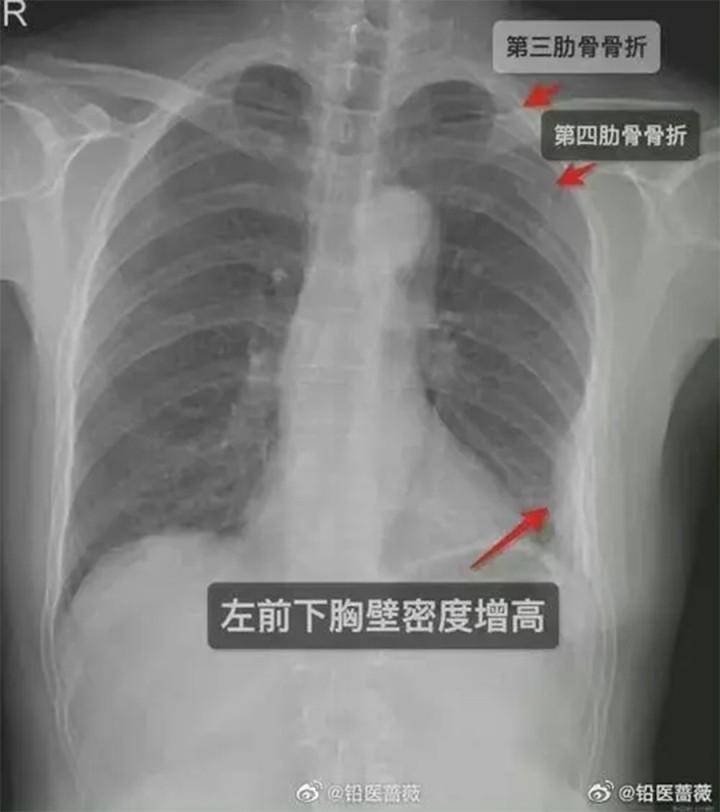

Phim X-quang của cô gái cho thấy có 3 cái xương sườn bị gãy.

Vào ngày thứ 5 sau sự việc trên, do đau đớn đến không thể chịu nổi, cô gái mới đến bệnh viện khám và hoảng hốt khi bác sĩ cho biết cô bị gãy 2 xương sườn trước bên phải và một xương sườn bên trái.